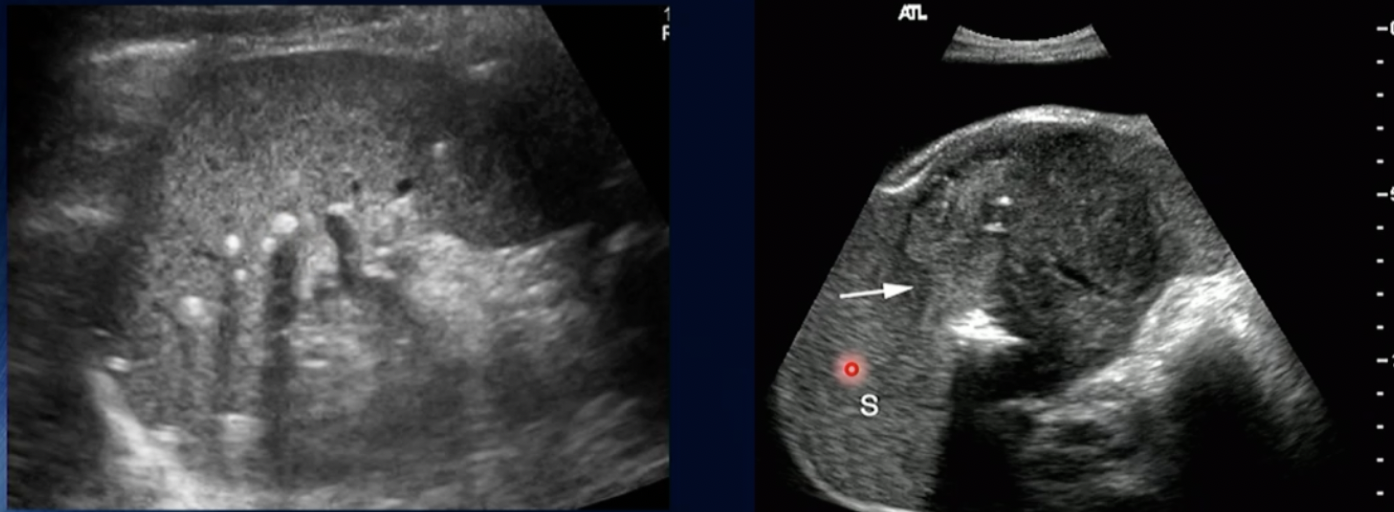

Path? (hint… SPLEEN)

Splenomegaly

Path?

Malignant Lymphoma of Spleen

Pathology?

Haemangioma (due to no colour on it)

HCC due to colour/bloodflow